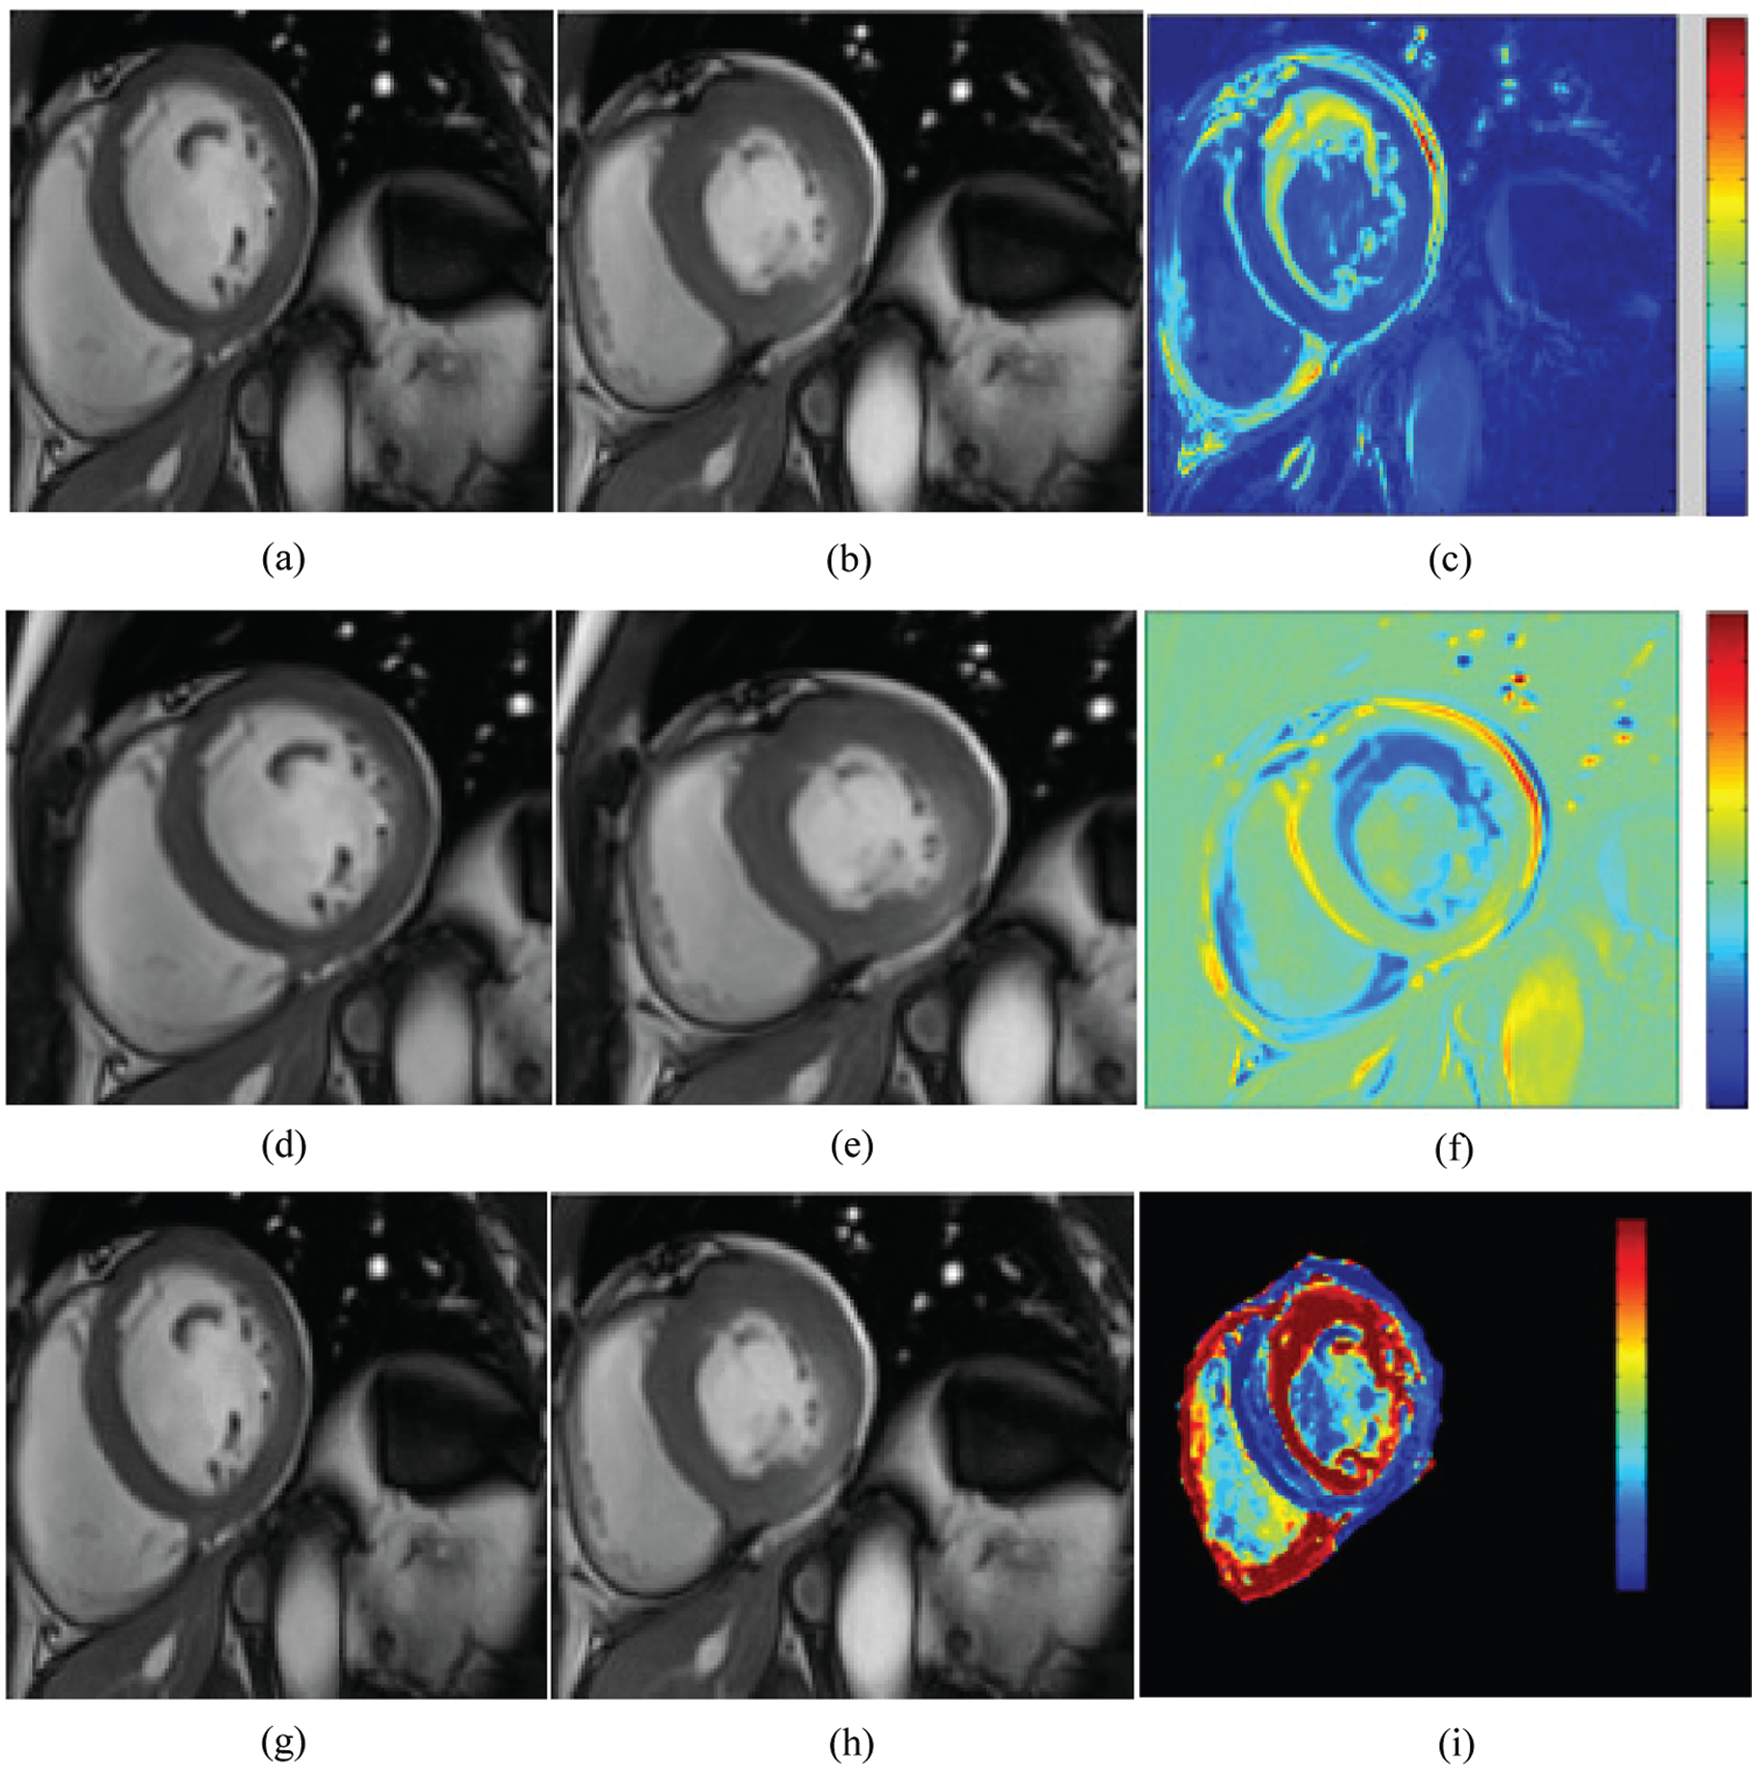

Fig. 6 shows an example of two frames of cine-MRI sequences with their corresponding parametric images computed respectively. The computation is done based on the monogenic signal, the Hilbert transform (top panel), and the covariance analysis (bottom panel) methods for a patient with myocardial infarction located in the inferior as well as inferolateral walls. Based on the Hilbert transform analysis, the parametric amplitude image shows a momentous variation of color intensity and different pattern, which was reflecting the presence of contractile dysfunction. Similarly, a decrease in the amplitude value have been revealed in the two parametric images. These two images were examined based on the monogenic signal and covariance analysis of the same patient. The decrease ratio is observed clearly in the images by a decreased intensity in the same sectors compared to the other myocardial areas. The qualitative and the quantitative analysis confirms that the location of wall motion abnormalities is the same for the three parametric amplitude images. Additionally, the regional heterogeneity of contraction amplitude was easily identified using parametric image with the monogenic signal where a significant change of color distribution was depicted in the segments with reduced contraction. The covariance analysis was less helpful for the identification of segments with myocardial dysfunction where Fig. 6i shows a little change of myocardial thickness while the color is kept the same.

A visual inspection of Fig. 7 shows a homogeneous distribution of contraction ‘amplitude along the myocardium. The three approaches reveal similar results of contraction amplitude, which approve the normal aspect of the myocardium. This observation was confirmed by the circumferential map obtained from strain analysis (Fig. 7c) where there is a uniform color distribution in the different myocardial segments. The blue color that characterizes the entire myocardium in the circumferential map reveals normal strain values.

Figure 6: Cine MRI images at the two instants: end-diastole (a, d, g) and end systole (b, e, h) with the corresponding parametric images computed from the Hilbert transform (c), the monogenic signal (f), and the covariance analysis (i) for a subject with myocardial infarction. A significant change of color distribution and myocardial thickness were depicted in the same segments (the inferior and inferolateral segments) of parametric images

Figure 7: Cine MRI images at the two instants: end-diastole (a) and end systole (b) with the corresponding circumferential strain map (c) and parametric images computed from the monogenic signal (d), the Hilbert transform (e), and the covariance analysis (f) for a healthy subject